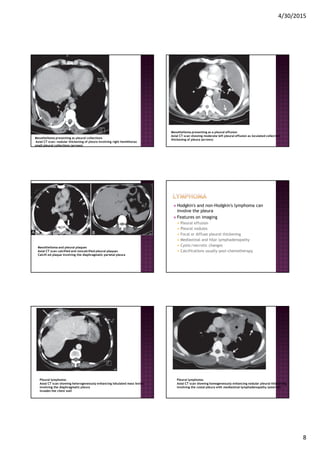

Mesothelioma presenting as pleural collections

Axial CT scan: nodular thickening of pleura involving right hemithorax

small pleural collections (arrows)

Mesothelioma presenting as a pleural effusion

Axial CT scan showing moderate left pleural effusion as loculated collection

thickening of pleura (arrows)

Mesothelioma and pleural plaques

Axial CT scan calcified and noncalcified pleural plaques

Calcifi ed plaque involving the diaphragmatic parietal pleura

Hodgkin's and non-Hodgkin's lymphoma can

involve the pleura

Features on imaging

Pleural effusion

Pleural nodules

Focal or diffuse pleural thickening

Mediastinal and hilar lymphadenopathy

Cystic/necrotic changes

Calcifications usually post-chemotherapy

Pleural lymphoma:

Axial CT scan showing heterogeneously enhancing lobulated mass lesion

involving the diaphragmatic pleura

invades the chest wall

Axial CT scan showing homogeneously enhancing nodular pleural thickening

involving the costal pleura with mediastinal lymphadenopathy (asterisk)